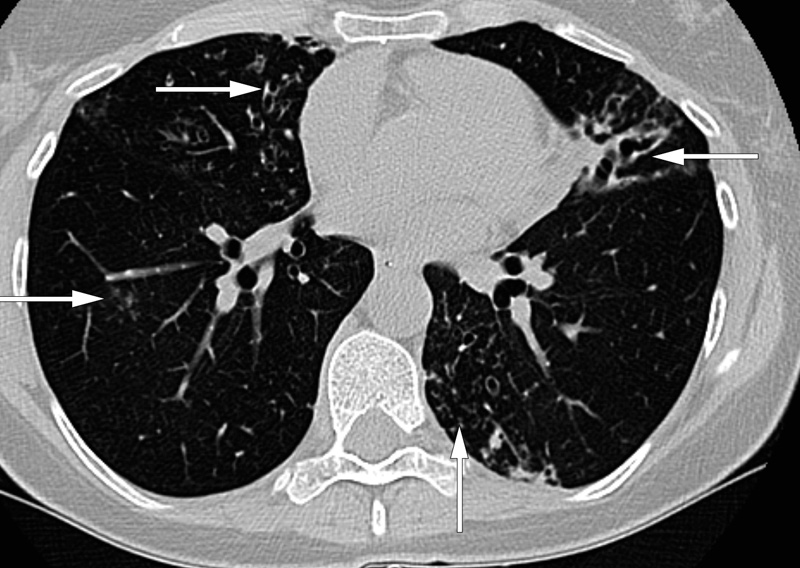

En tidligere frisk kvinne i 40-årene hadde hatt flere episoder med hemoptyse. Utredning med røntgen thorax og CT thorax ved et privat institutt hadde vist diffust avgrensede sentrilobulære noduli, dels omgitt av løst mettede, alveolære fortetninger (mattglassforandringer) basalt i begge overlapper og en ektatisk bronkialgren basalt i venstre overlapp. Dessuten forelå det en liten kavitet sentralt i høyre overlapp.

Det ble utført bakteriologisk undersøkelse og direkte mikroskopi av sputum. Dyrkning viste primært normalflora, men seks uker etter innleggelsen kom det positivt dyrkningssvar for Mycobacterium avium-kompleks (MAC). Pasienten fikk trippelbehandling (klaritromycin, etambutol og rifampicin) i to år, men den ble avsluttet grunnet fortsatt positive dyrkninger og progredierende radiologiske funn. I forløpet frem til seneste CT-kontroll syv år etter første innleggelse er det kommet til gradvis økende, multifokale bronkiektasier samt økt kavitetsdanning i høyre overlapp (bildet). Hun følges fortsatt poliklinisk – det kliniske bildet er relativt stabilt og hun har tilfredsstillende lungefunksjon.

Typiske radiologiske funn ved MAC-infeksjoner er multiple nodulære fortetninger, multifokale bronkiektasier og kaviteter (4). Tidlig diagnostikk og rask oppstart av behandling kan være av betydning for graden av irreversibel luftveisskade. CT thorax er følsom for tidlige parenkymforandringer, og et nært samarbeid mellom infeksjonsmedisiner og radiolog kan bidra til raskere diagnose.